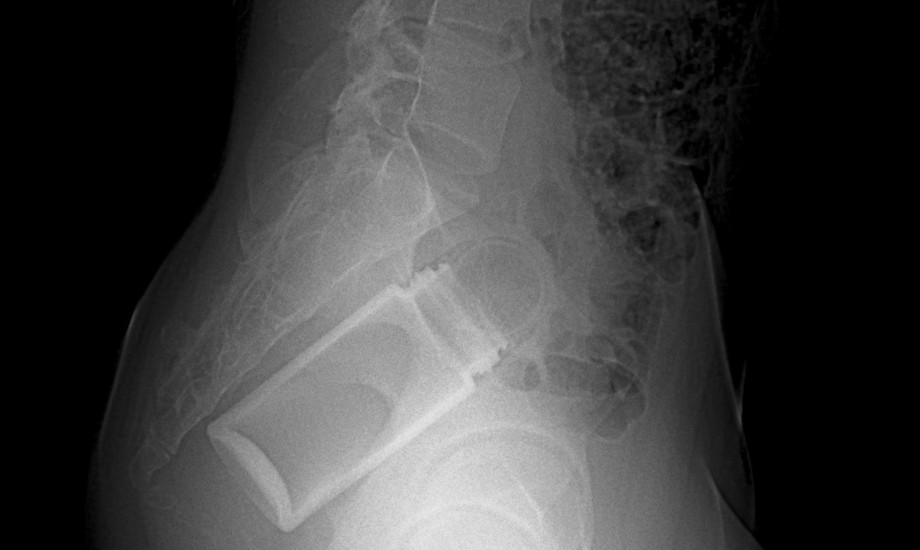

Rektale Fremdkörper sicher entfernen und gezielt nachsorgen

Ein im Rektum verbliebener Fremdkörper ist ein selten offen kommuniziertes, in der Notfallmedizin jedoch durchaus relevantes Krankheitsbild. Die Versorgung erfordert neben technischem Können vor allem strukturiertes Vorgehen und Sensibilität im Umgang mit den Betroffenen.